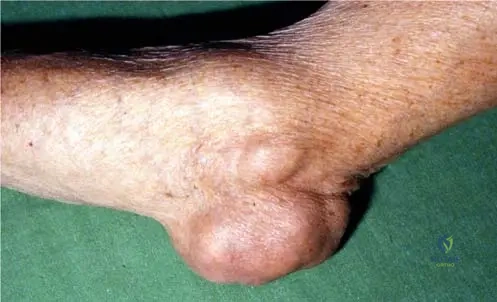

A 70-year-old male with a long history of gout presents with a large, firm, non-tender mass over his left elbow. Examination reveals significant swelling and a palpable nodule in the olecranon region. This finding is consistent with a massive tophaceous deposit of urate crystals. Which image best illustrates this specific presentation?

View Answer & Explanation

Correct Answer: D

Rationale: Fig. 7.9 is explicitly labeled "Bursitis olecrani due to the massive tophaceus deposit of urate crystals." This perfectly matches the clinical vignette describing a tophaceous mass over the olecranon. The other images depict chronic hand gout, subcutaneous tophi in the palm, acute knee gout, or intraoperative findings, not specifically olecranon bursitis.

Question 43

Question 58